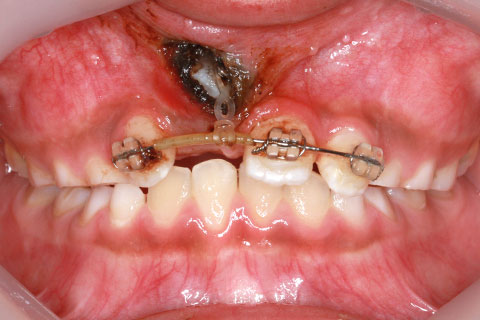

治療中

歯肉切除により歯冠を露出させて引っ張り出す治療法

右上1番を露出させるため、歯肉切開が必要になるため、外科処置における疼痛や腫脹のリスクを説明した。また、右上1番を牽引しても理想的な位置にもっていけない場合もあると説明。